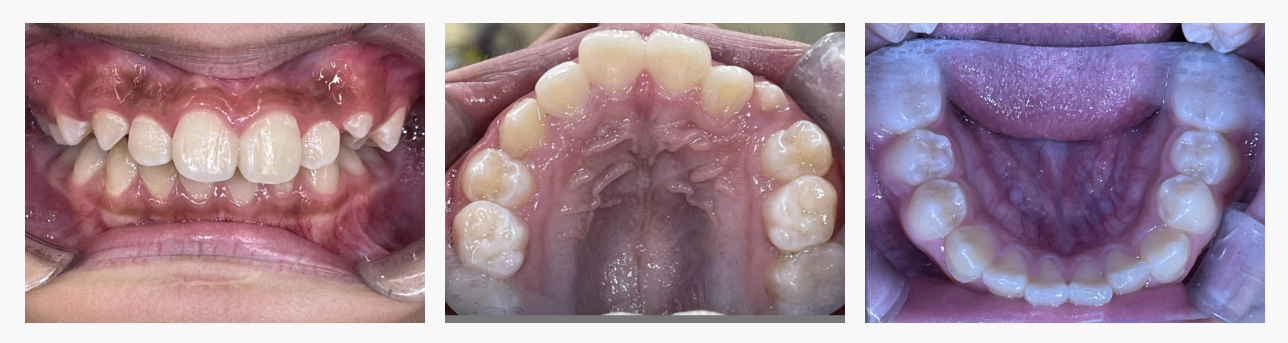

▼ After(治療後)

◆ 治療の結果

マイオブレイスによる機能改善と成長誘導により、

・ガタガタの改善

・上の前歯の突出の軽減

・口元のバランス改善

・鼻呼吸の定着、正しい舌位置の獲得

など、多面的な改善がみられました。

歯を強制的に動かすのではなく、お子さま自身の成長力を活かす小児矯正ならではの良好な結果です。